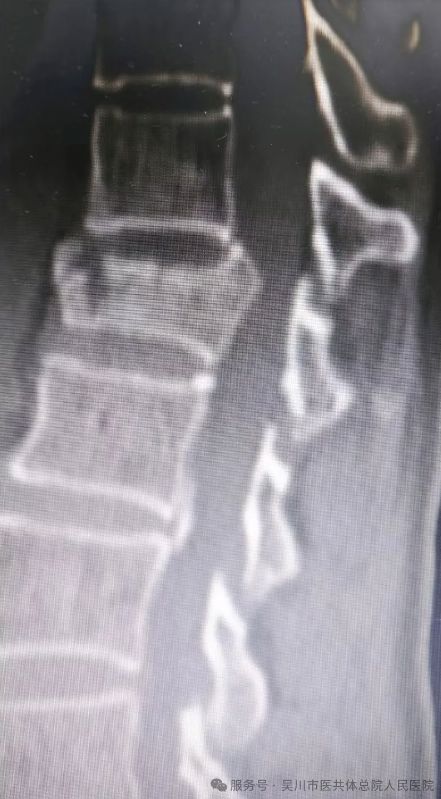

图片

外伤骨折急救治,微创复位助康复

近日,63岁的沈女士不幸被大树砸伤,导致胸12椎体压缩性骨折,骨折块后突压迫椎管,相应脊髓受压变性,出现左下肢放射痛、麻木及肌力下降等症状,若不及时干预可能导致严重后遗症。

骨外科三区主任、主任医师曾维,主管医生宁健文迅速组织科室团队制定救治方案,决定为其实施 “胸12椎体骨折切开复位钉棒内固定术+后路减压术”。该科医护团队凭借丰富的临床经验与精准的操作技巧,成功复位骨折椎体、解除椎管压迫。

术后,沈女士左下肢放射痛、麻木症状逐渐减轻,肌力稳步恢复,看着身体一天天好转,她感慨道:“是曾主任和骨外科三区团队给了我重新站起来的希望!”